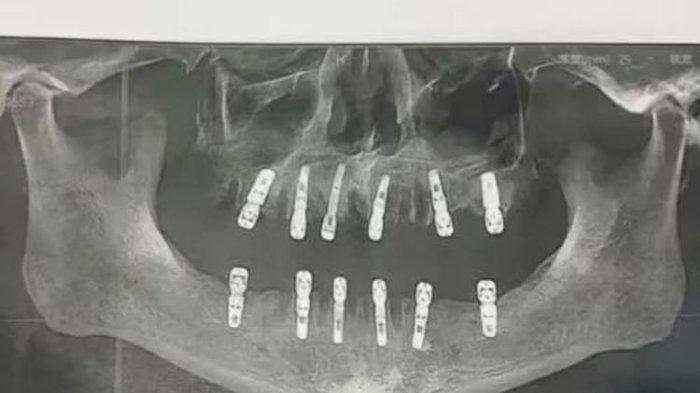

Diketahui sang pria ini melakukan tindakan cabut 23 gigi lalu memasang 12 gigi implan.

Shu, anak Huang, melaporkan kasus tersebut setelah menemukan bukti formulir yang menyatakan bahwa orangtuanya bersedia mencabut 23 gigi dan memasang 12 gigi baru.

Prosedur medis yang dilakukan dengan membuat lubang di tengkorak dan rahang bawah dalam satu hari itu dikenal sebagai "immediate restoration" atau "restorasi segera".

Menurut catatan DeWay Dental, 23 pencabutan gigi tersebut dilakukan oleh seorang dokter, yang merupakan dokter gigi spesialis perawatan saluran akar, gigi bungsu impaksi, dan gigi palsu lengkap.